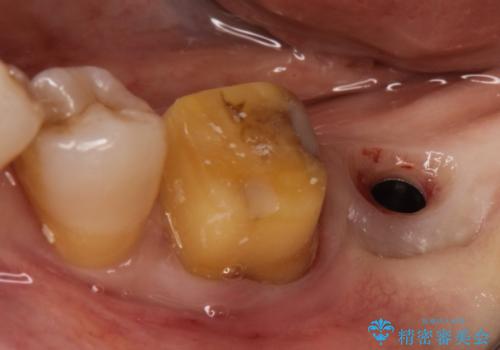

- 左下の1番後方の歯が欠損しており、インプラントにて咬合回復する計画としました。

レントゲン・CT撮影により骨の高さがあまりないことがわかり、ショートインプラントを選択しました。

また、清掃性を確保するために歯肉の移植も行うこととしました。